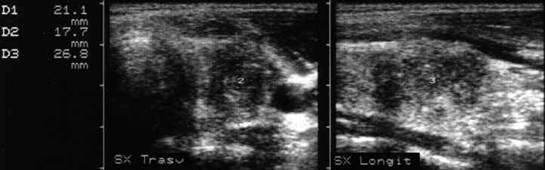

Carcinom ANAlaZic.Recidiva laterocervicalA

Femeie de 73 ani. Recidiva laterocervicala dreapta

dupa meta de carcinom anaplazic.

Prima imagine este efetuata la 3 luni dupa interventia chirurgicala si evidentiaza

o leziune de 20x23x24mm (5,7 cc).

A doua imagine s-a efectuat la 25 de zile dupa prima; leziunea masoara 33x42x40mm,

(29 cc).

Examen citologic: carcinom anaplazic.

Aceeasi pacienta - vascularizatie slaba la doppler datorata necrozei.